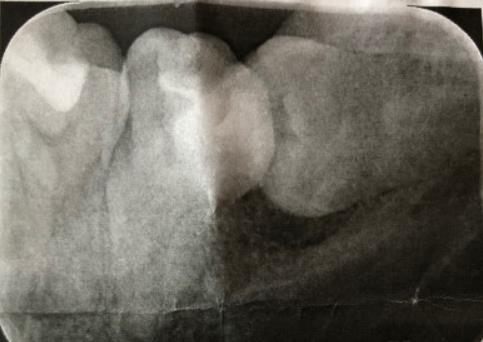

智齒拍片

深圳愛康健口腔醫院醫生解釋,拔牙是采用全景數字掃描設備對口腔全麵掃描,確定需要拔除的牙齒位置,然後準確局部麻醉,在不損傷(shang) 牙齒以及周圍牙周組織的前提下,將牙齒拔出。